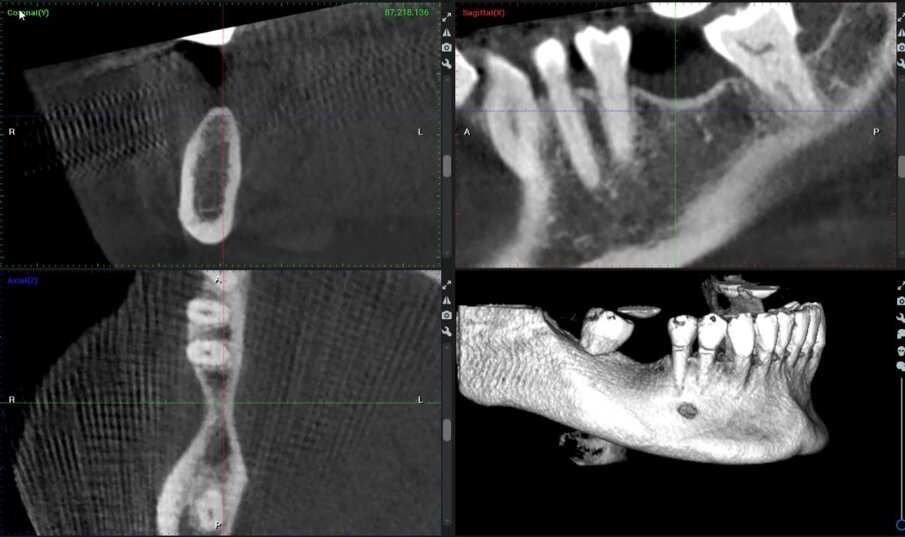

Una paziente di 51 anni di sesso femminile ha frequentato la nostra clinica cercando una riabilitazione in un sito edentulo inferiore 46. L’elemento dentale 46 è stato estratto più di 4 mesi prima della consulenza e non è stato utilizzato alcun materiale per la conservazione dell’alveolo. La paziente era una non fumatrice in buona salute, senza malattie parodontali (nessuna perdita di attacco, tasche al sondaggio e BoP). È stato eseguito un esame pre-operatorio con tomografia computerizzata a fascio conico (CBCT) nel quarto quadrante inferiore, che ha rivelato una significativa perdita ossea orizzontale nella zona edentula (Fig. 1). La densità ossea è stata classificata come tipo 2 e la distanza dal margine alveolare più coronale al canale alveolare inferiore era sufficiente per posizionare un impianto dentale (più di 10 mm) (Fig. 1). L’esame clinico ha rivelato una larghezza del tessuto cheratinizzato di più di 4 mm sulla cresta comunque sottile (Fig. 2). Il paziente è stato trattato con la tecnica del Poncho Lamina per un processo di ottimizzazione in un solo passo (Processo O.S.O.) nel sito 46. In questo caso, abbiamo selezionato e utilizzato un impianto MIS V3 (MIS Implants Technologies) e una ben documentata barriera corticale Soft Lamina 25x25 (Osteobiol by Tecnoss). L’ottimizzazione del tessuto molle è stata ottenuta con un moncone personalizzato generato tramite il sistema VPI Cervico (VP Innovato Holdings).

Fig. 1_Immagini CBCT pre-operatorie del sito 46.

Ri-valutazione radiologica

Le immagini CBCT sono state ottenute utilizzando un sistema di radiografia computerizzata CS8100 3D Carestream (Carestream Health) con una dimensione di voxel di 0,150 mm e un campo visivo di 8x9 cm prima (T1) e 16 settimane (T2) dopo l’inserimento dell’impianto. I file originali in formato DICOM sono stati importati nel software Romexis (Planmeca) per l’analisi. Per entrambi i set di dati T1 e T2, abbiamo selezionato per la valutazione delle sezioni trasversali nel mezzo del sito sulla sezione assiale e perpendicolare alla cresta alveolare (Fig. 25).

Fig. 25_a), b): Immagini coronali e assiali CBCT prima dell’intervento chirurgico e a 4 mesi dopo l’intervento.